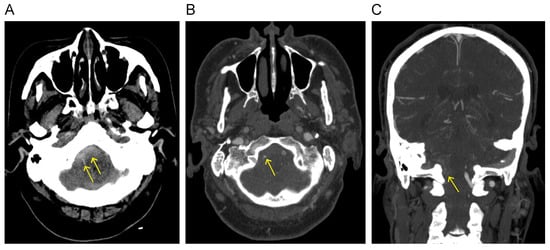

3.2.2. Radiological Findings